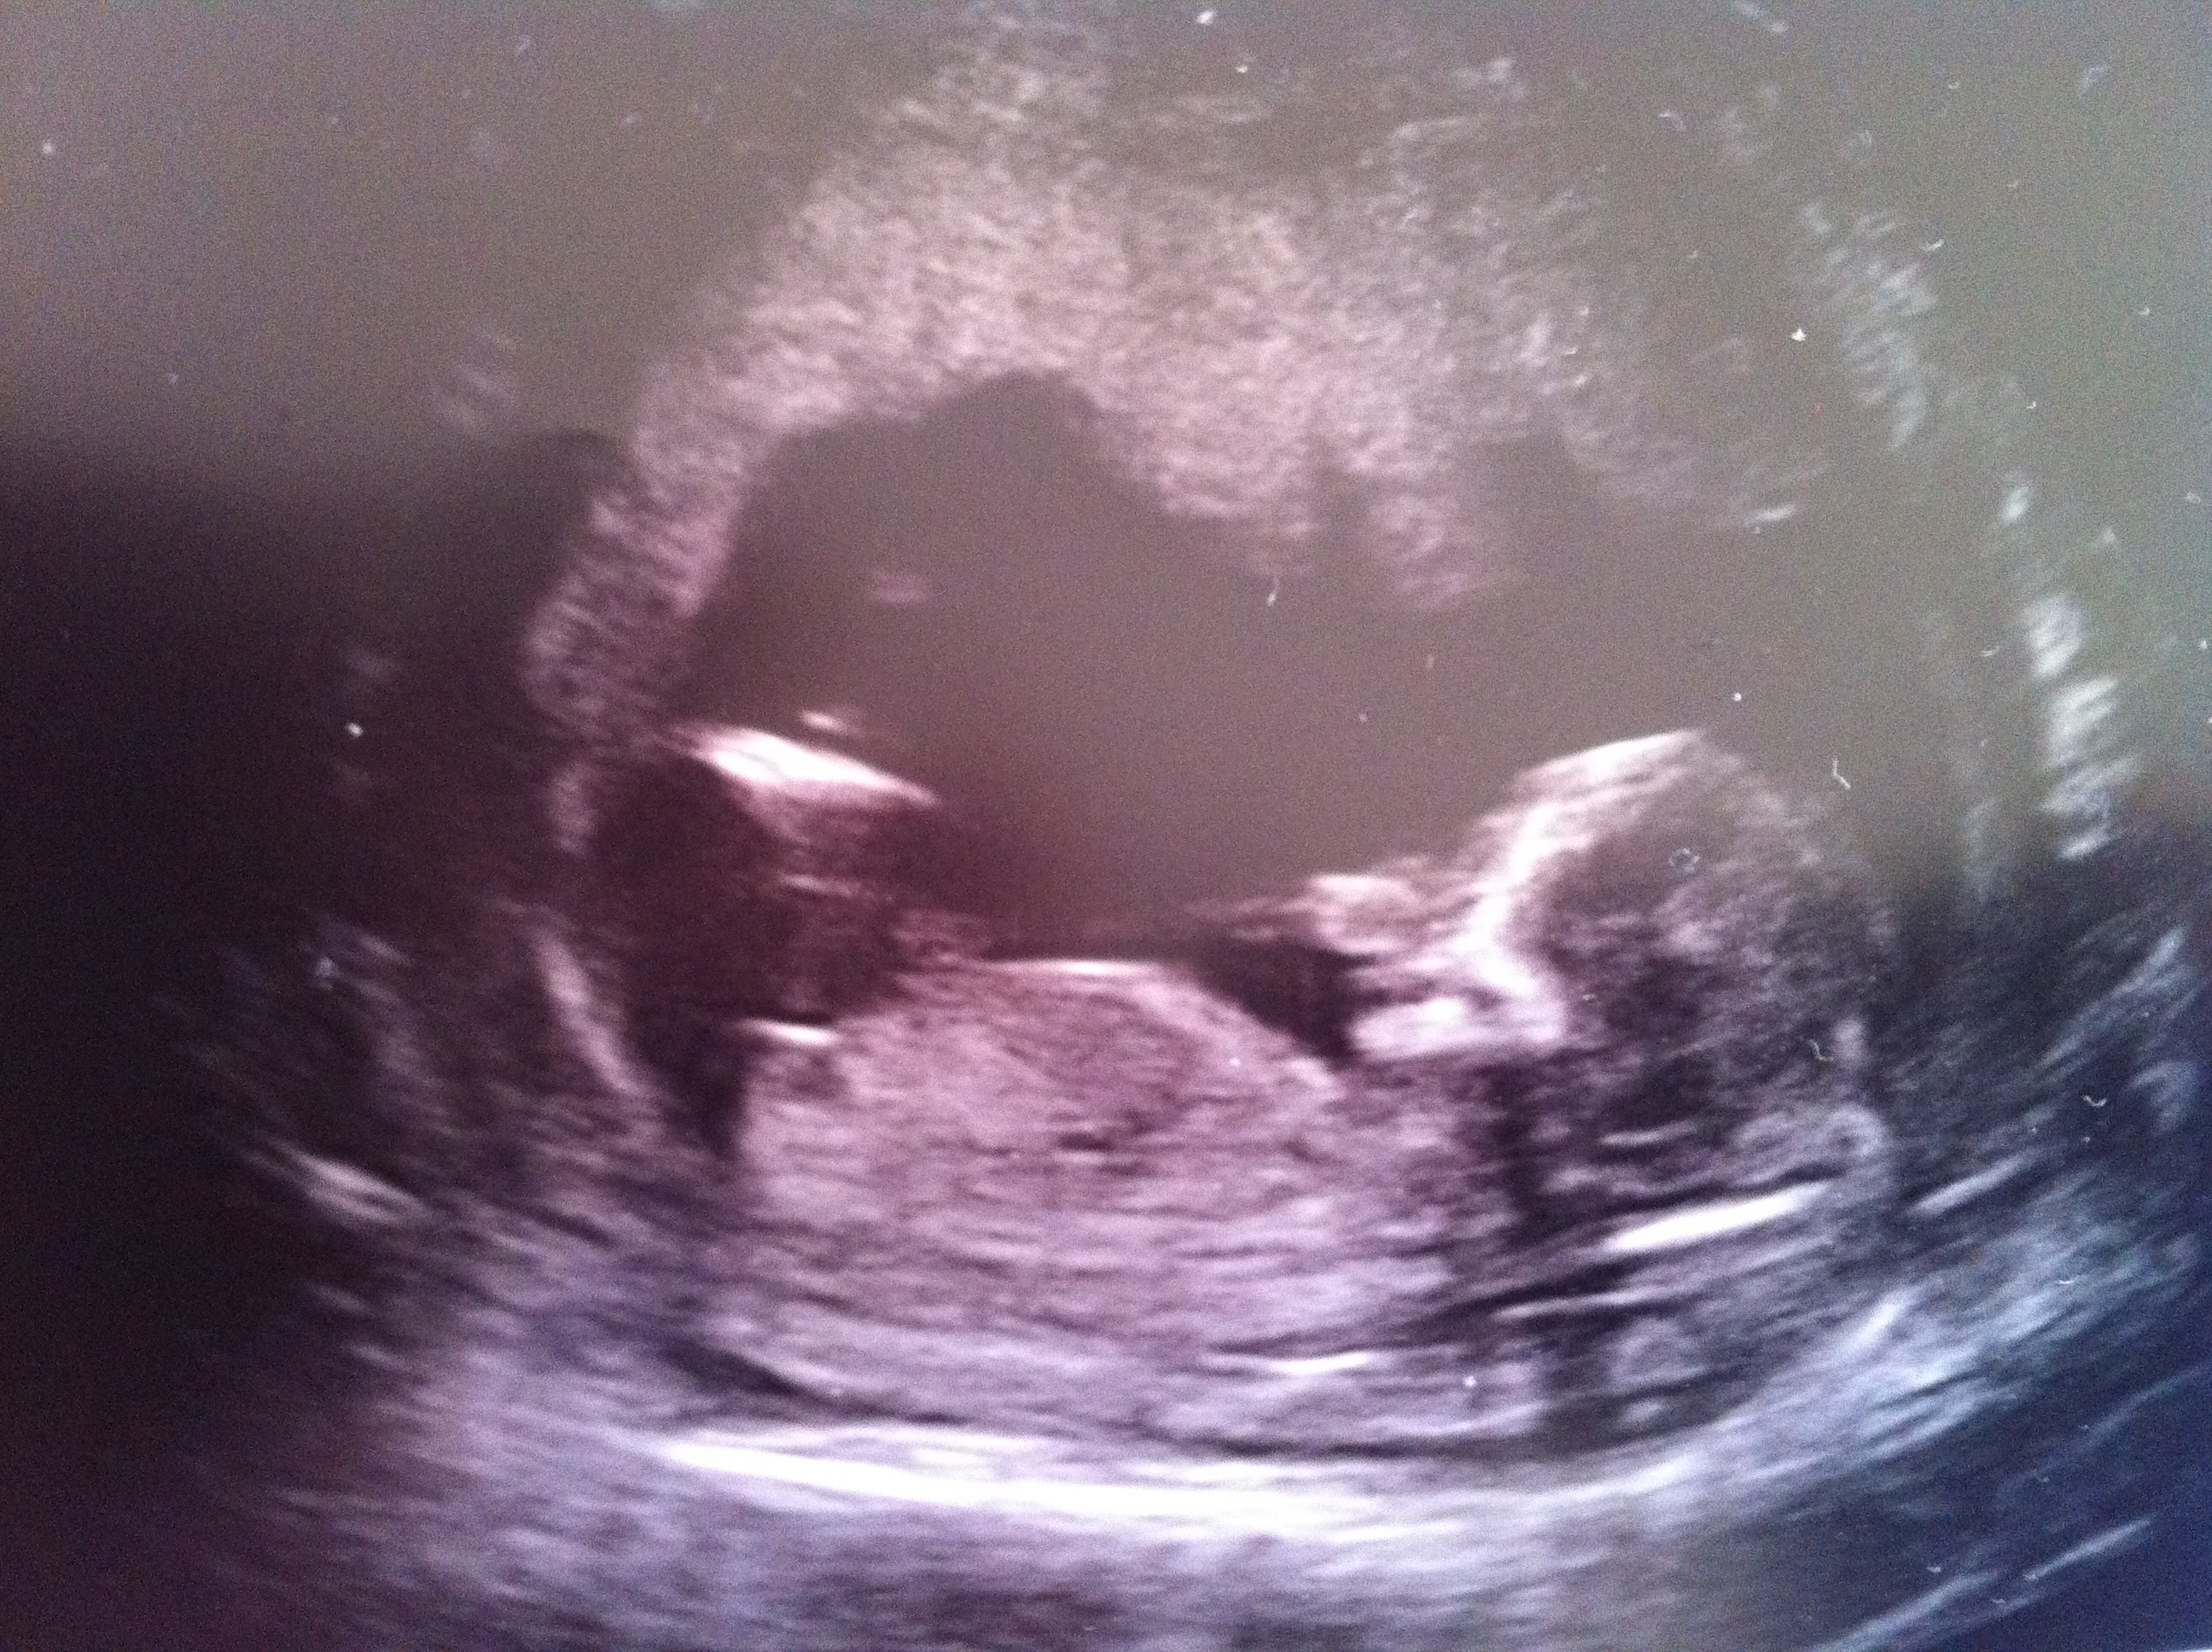

Girl

Very flat girly nub there!

Thankyou ladies for having a look. Your opinions are very much appreciated. Can't believe I was lucky enough to be given pictures which included the nub. It was very obvious during the scanning that the nub was long and flat. When I saw the potty shot there was definitely nothing between the legs. All I saw was a flat horizontal bright White line? I was to afraid to ask for a gender guess and won't be finding out at the next scan either. X